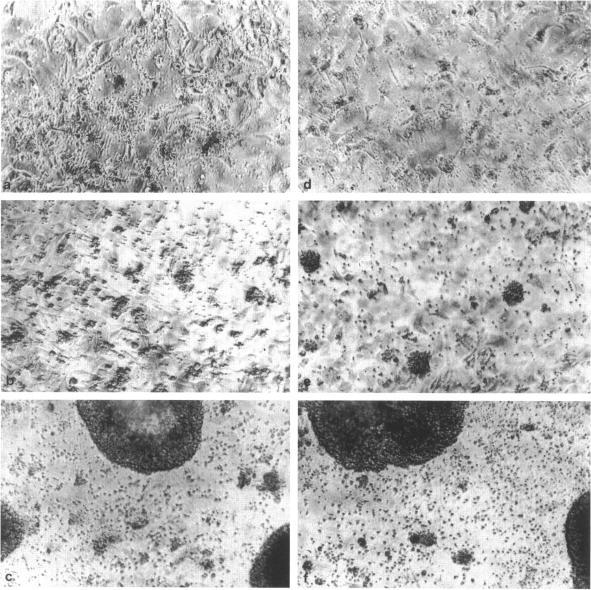

To investigate the mechanisms of T cell dependence underlying the development of extranodal mucosa-associated lymphoid tissue (MALT)-type B cell lymphomas, the activation, proliferation, and differentiation of lymphoma B cells were studied using ligand binding to the CD40 membrane receptor. The activation and proliferative response of all investigated low-grade MALT-type lymphomas (n = 6) was strongly dependent on anti-CD40-mediated signals and was complemented by cytokines produced by T helper cells of the Th2 type (interleukin-4 (IL-4) and/or IL-10). Th1 cytokines (IL-2 and/or interferon-gamma) bad little effect. Low-grade, but less so high-grade, MALT-type lymphoma B cells were induced to secrete large amounts of tumor immunoglobulin in response to IL-10. In contrast, high-grade MALT-type lymphomas (n = 5) proliferated in response to both Th2- and Th1-type cytokines and CD40 stimulation, whereas Burkitt lymphomas (n = 3) could not be rescued from apoptosis by CD40 stimulation with or without cytokines. These results suggest that CD40 signaling in combination with Th2 cytokines are essential for the development and progression of low-grade MALT-type B cell lymphoma. We conclude that T cells, which activate B cells in a CD40-dependent fashion, may contribute to lymphoma pathogenesis.